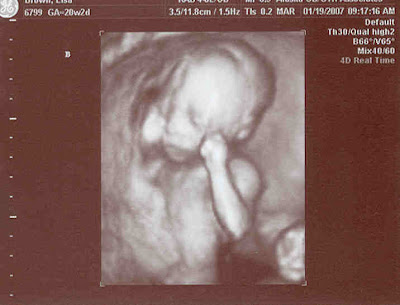

Our babies have been diagnosed with TTTS (twin-to-twin transfusion syndrome). I'll copy an explanation from a website so I don't mess anything up.

"Twin-to-twin transfusion syndrome (TTTS) is the consequence of unbalanced blood flow from one twin (the donor) to the other (the recipient) across transplacental vascular communications and results in the polyhydramnios/ oligo- hydramnios sequence and can include growth discordance."

In other words, the blood flow from baby to baby is connected via the placenta. One baby is working harder and forcing the fluid to the other baby's amniotic sac. If untreated, the fluid is drained from the donor's sac and will die of dehydration. The recipient may also die because she can't cope with the extra blood flow so her heart will fail.